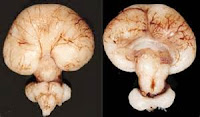

There is a malformation of the brain during the first four weeks of embryogenesis. It results in an incomplete cleavage of the cerebral hemispheres. The Sonic Hedgehog protein is necessary for the development of the forebrain. It helps establish the line that separates the right and left sides of the forebrain. Specifically the midline for the underside of the forebrain, making the ventral surface (SHH gene, 2016).